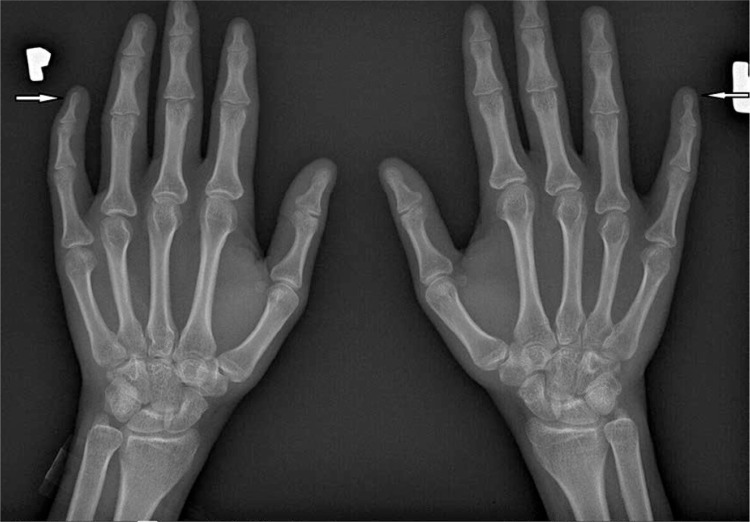

系统性硬化症(SSc)是一种多器官、全身性结缔组织疾病,会影响肺、心脏、胃肠道、肾脏、皮肤和肌肉骨骼系统。40%-90%的 SSc 患者会出现肌肉骨骼受累。患病期间,骨骼、关节、腱鞘、肌腱和肌肉等肌肉骨骼系统的任何结构都可能受到影响。最常见的症状包括关节疼痛、关节炎、导致肌腱断裂的肌腱炎、关节骨溶解、钙化、肌痛和肌炎。骨关节并发症和手部软组织的变化会导致手指挛缩,从而导致患者生活质量下降和残疾。总之,更详细地了解导致肌肉骨骼系统渐进性变化的病因,可能有助于引入新的治疗方案,从而改善 SSc 患者的生活质量并减少残疾。

Systemic sclerosis (SSc) is a multi-organ, systemic connective tissue disease, which affects the lungs, heart, gastrointestinal tract, kidneys, skin, and musculoskeletal system. Musculoskeletal involvement is observed in 40-90% of patients with SSc. During the disease, any structure of the musculoskeletal system, such as bones, joints, tendon sheaths, tendons, and muscles, may be affected. The most common symptoms include joint pain, arthritis, tendinitis leading to tendon rupture, acro-osteolysis, calcinosis, myalgia, and myositis. Osteo-articular complications and changes in the soft tissues of the hand lead to finger contracture, which causes deterioration of the patients' quality of life and disability. To sum up, a more detailed understanding of the aetiology leading to progressive changes in the musculoskeletal system may contribute to the introduction of new therapeutic options, and thus improve the quality of life and reduce disability in patients with SSc.